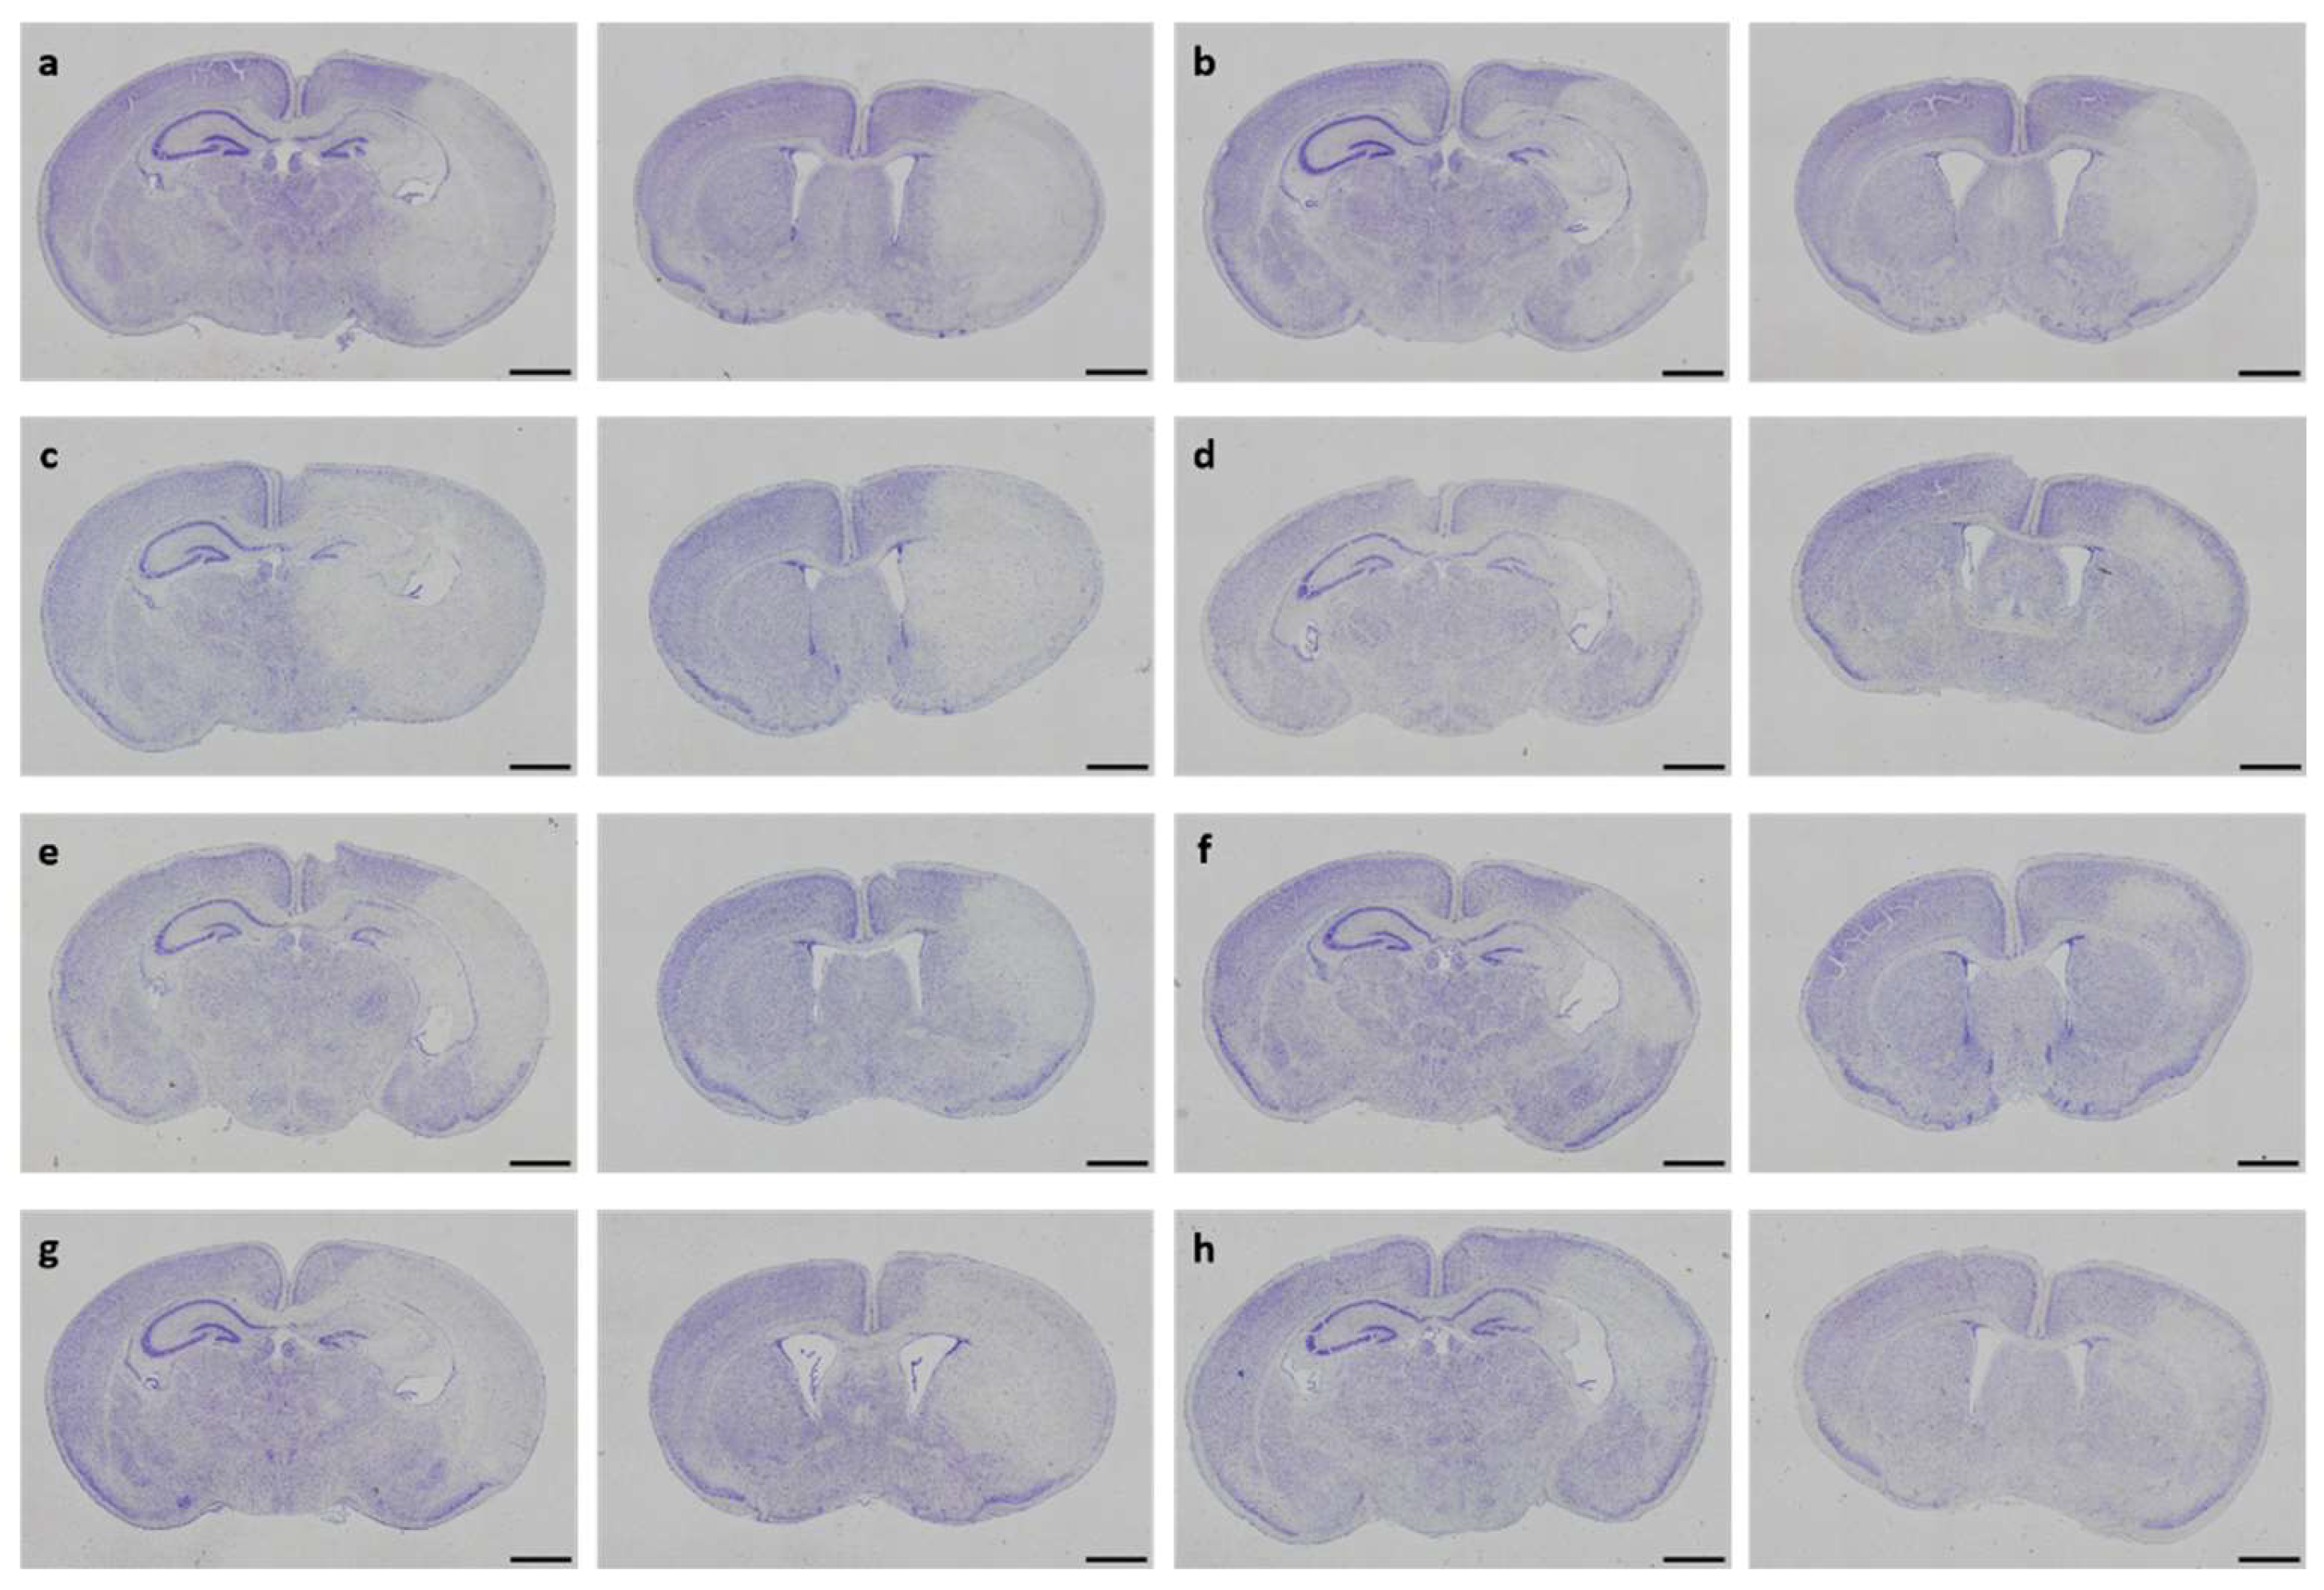

3.2. Neuropathological Injury